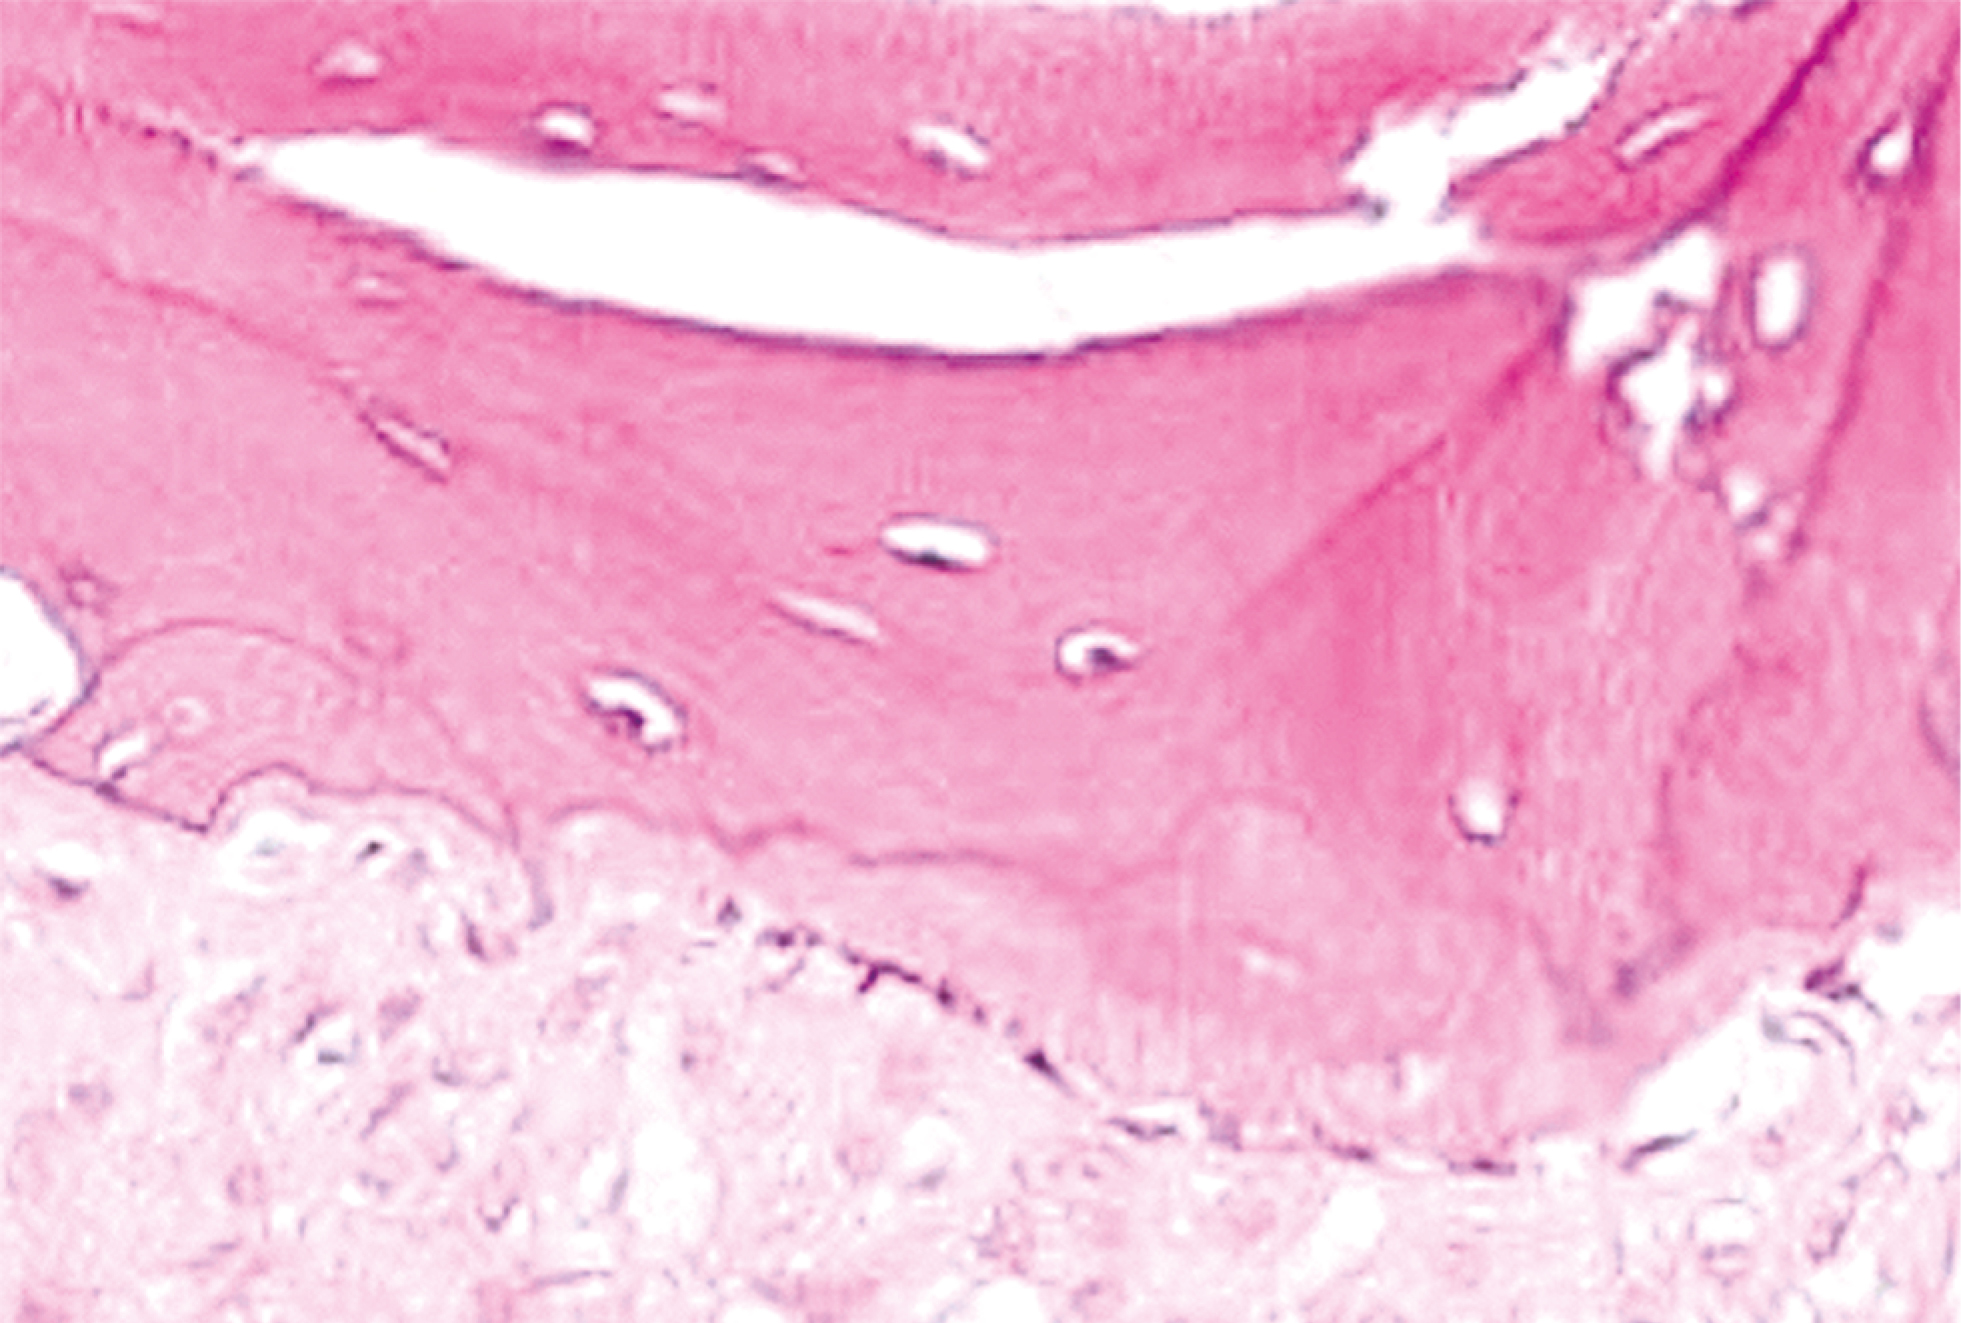

Пациентам 2-й группы (рис. 3) применяли комбинацию материалов Bio-Oss, Bio-Gide (Geistlich Pharma AG, Швейцария). Отмечается хороший показатель плотности кости. При гистологическом описании наблюдается наличие небольшого количества остеобластов, визуализируются остеоидные структуры, молодые костные трабекулы, базофильные участки с хаотично расположенными коллагеновыми волокнами (рис. 4).

Рис. 4. Срез новообразованной костной ткани после применения комбинации костнопластических материалов Bio-Oss, Bio-Gide. Окраска гематоксилином и эозином

При исследовании гистологических срезов, окрашенных гематоксилином и эозином, отмечается активный остеогенез с формированием трабекулярной кости, резорбцией трансплантата и его замещением зрелой костной тканью (рис. 6).

Рис. 6. Новообразованная костная ткань после применения комбинации материалов bioOST, bioPLATE. Окраска гематоксилином и эозином